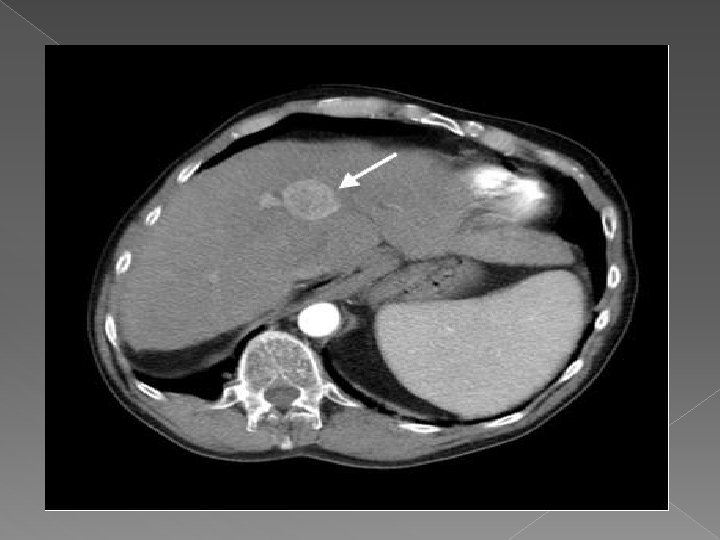

Computer tomografia Tehnica: -sectiuni contigui de 8 -10 mm, 5 mm pentru hil si cai biliare -nativ +contrast: cu rol in diferentierea leziunilor de parenchimul normal q Leziunile focale • Sunt de regula spontan hipodense • Incarcare mai mica decat a parenchimului hepatic Exemple: v Tumori hepatice-primitive sau secundare v Chiste; v Abcese; v Hematoame; v Steatoza.

Hemangiom hepatic